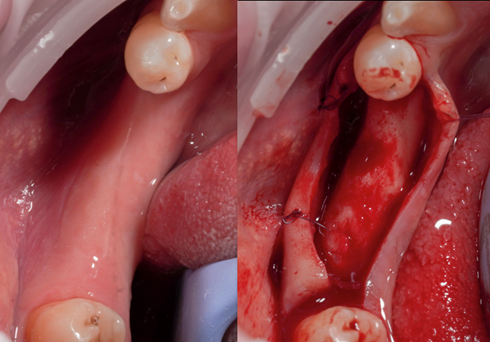

• Živý zákrok na pacientovi

• 13:00 – 14:30 LIVE zákrok soloimplantace na pacientovi.